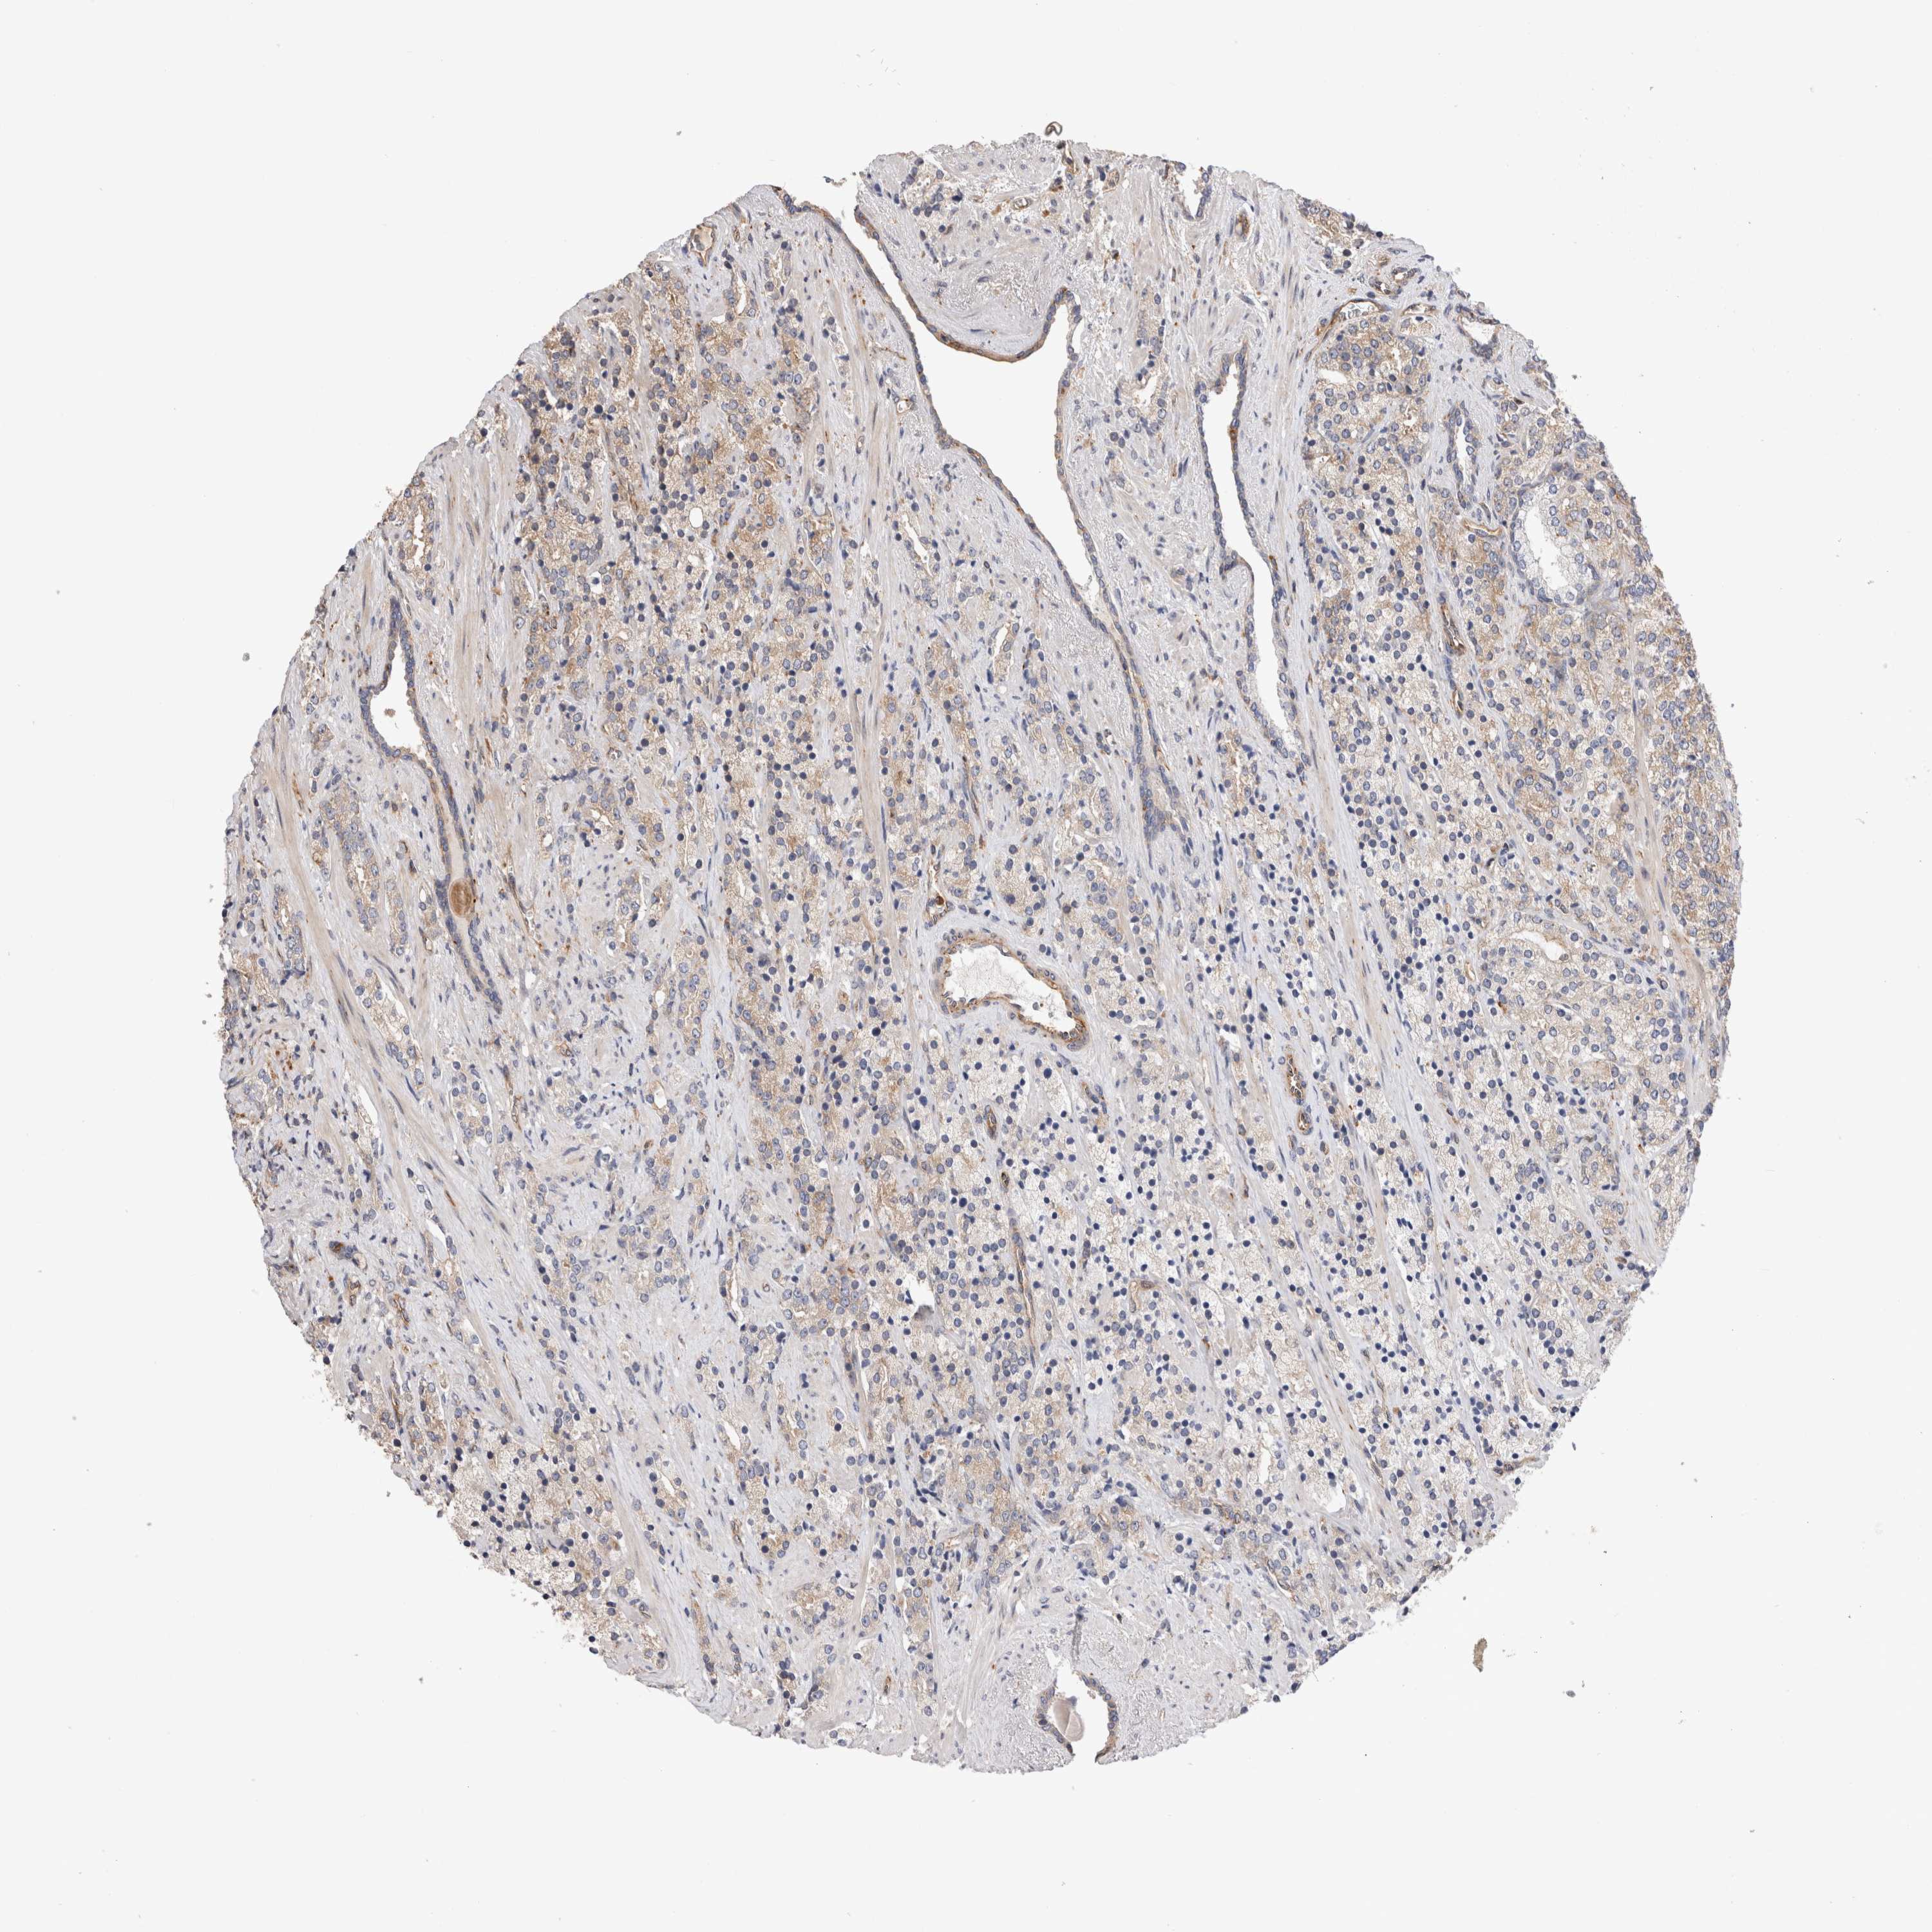

PROSTATE CANCER - Protein expressioni

A mouse-over function shows sample information and annotation data. Click on an image to view it in a full screen mode. Samples can be filtered based on level of antibody staining by selecting one or several of the following categories: high, medium, low and not detected. The assay and annotation is described here.

Antibody stainingi

Antibody staining in the annotated cell types in the current human tissue is reported as not detected, low, medium, or high, based on conventional immunohistochemistry profiling in selected tissues. This score is based on the combination of the staining intensity and fraction of stained cells.

Each image is clickable and will lead to virtual microscopy that enables deeper exploration of all samples and also displays staining intensity scores, fraction scores and subcellular localization as well as patient and tissue information for each sample.

Antibody HPA026843

Staining

High

Medium

Low

Not detected

Intensity

Strong

Moderate

Weak

Negative

Quantity

>75%

75%-25%

<25%

None

Location

Nuclear

Cytoplasmic/membranous

Cytoplasmic/membranous,nuclear

Adenocarcinoma, High grade

Adenocarcinoma, Low grade